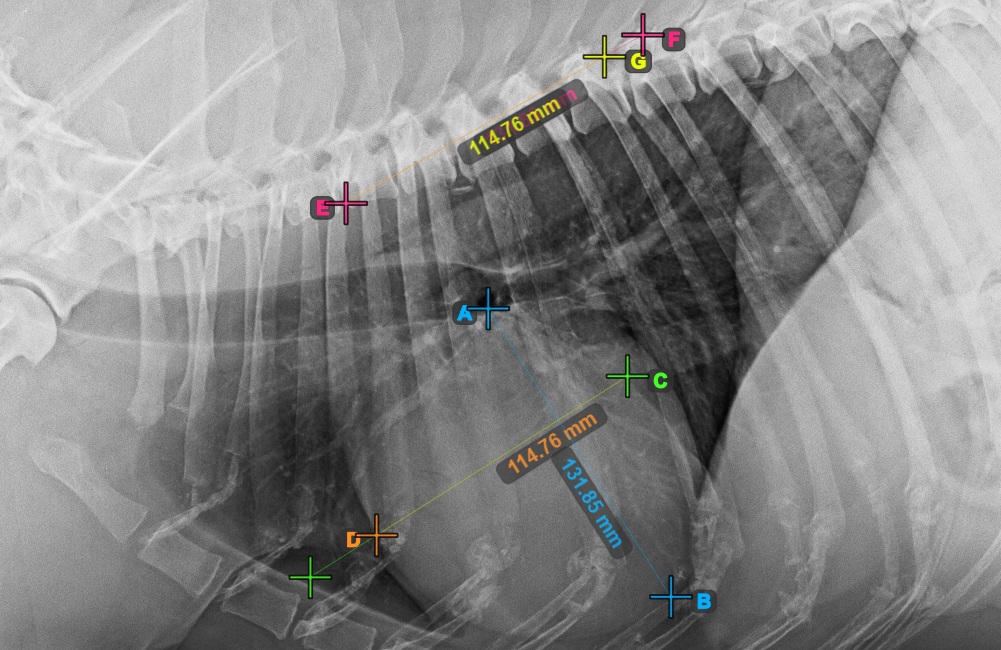

Identify the beginning of the T4 vertebra (the fourth vertebral body of the spine), counting from the initial point of the spine. Mark the beginning of the T4 vertebrae to continue the measurement. The software will draw lines from the marked point along the spine. The length of the lines depends on the measured long and short axes of the heart.

The image below represents the typical placement of the point at the beginning of the fourth vertebral body of the spine.

../../_images/image397.jpg

Before proceeding with the required VHS calculations, make sure that the lines are placed precisely along the vertebrae.

../../_images/image398.jpg